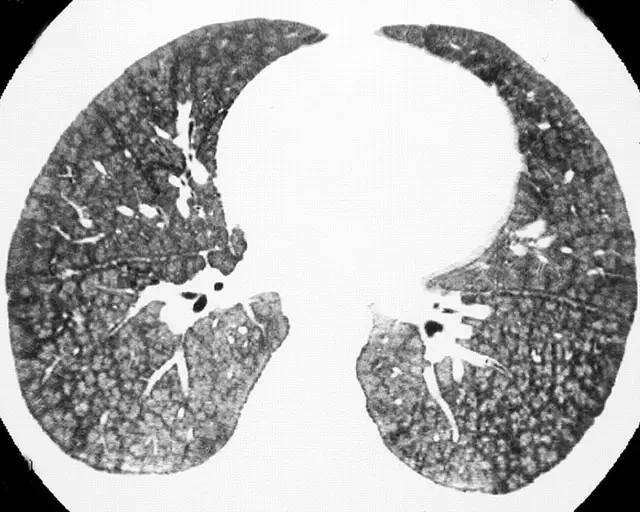

基本病史:女性,30 岁,自儿时起反复肺内出血病史,行高分辨率 CT 结果显示:

图 3 胸部高分辨率 CT 显示双肺弥漫性小叶中心型磨玻璃影和小叶中心型肺结节,部分结节边界清,部分边界不清,部分密度较高,但均未发现钙化密度